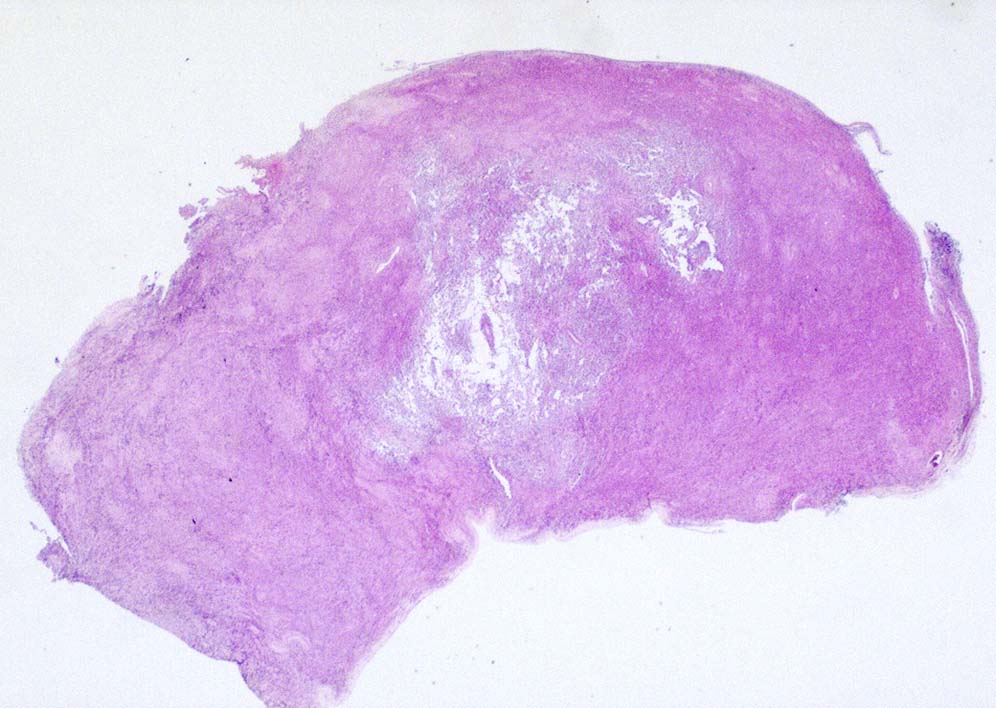

壁側胸膜腫瘤切除標本 病理組織所見

部分的に細胞接着性が低く疎な組織像を呈する.

① rhabdoid cellsが密に増殖する組織像. 核は類円形vesicularで, 中心性の大型核小体を1個もつ. 細胞質は好酸性.

球状の封入体様にみえる構造が出現し, 核偏在や核を圧排し, 三日月/半月状の核がみられている. mitosisが散在. 形質細胞が少数混在して認められる.

② 少量の線維性組織を間質に類円形/多稜形のvesicularな核と好酸性, 淡明な細胞質をもつ類上皮様の中~大型の細胞が集簇, 増殖している.mitosisが多い. 辺縁にはrhabdoid cellsのchohesiveな増殖が認められる.

③ 間質の線維組織が多く, 硝子化やmyxomatous changeが認められる. 二核の大型巨細胞が散在している. 細胞は比較的一様なサイズ形態で, 多型は高度ではない印象.